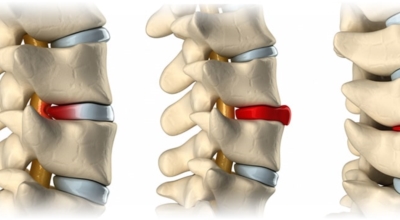

여러 개의 작은 척추뼈가 모여서 척추라는 신체의 기둥을 이루게 돼요. 척추뼈 사이에는 척추뼈끼리 부딪치는 것을 방지하는 쿠션 같은 역할을 하는 '디스크(disc)'라는 말랑말랑한 젤리 같은 구조물이 있는데 우리말로는 '추간판'이라고 합니다.

디스크(추간판)의 한가운데에는 젤리같이 찐득찐득한 '수핵'이라 하는 물질이 들어 있어요. 그 주변에 수핵을 둘러싸는 '섬유륜'이라 하는 두꺼운 막이 있는데 디스크는 전체적으로 자동차의 타이어와 같은 형태라고 합니다.

디스크는 일어선 상태에서는 중력을 받아 납작해져서 바깥쪽으로 약간 볼록한 형태가 된다고 합니다. 디스크는 그 특수한 구조 때문에 웬만한 힘이 가해져도 효율적으로 쿠션 역할을 할 수 있겠습니다. 그러나 급작스럽게 무거운 물건을 들어 올리거나, 부자연스러운 자세를 오랜 시간 취하면 디스크에 무리한 힘이 가해지면서 디스크가 밖으로 돌출이 되게 돼요. 심한 경우 디스크를 감싼 막이 터지면서 그 안에 있는 수핵이 튀어나오게 돼요.

디스크는 대개 후방이나 후외방으로 돌출되는데 이때 바로 곁에 있는 신경을 누르게 된다고 합니다. 돌출된 디스크는 척추의 어느 부위에나 일어날 수 있어요. 목에 생기면 '목 디스크', 등에 생기면 '등 디스크', 허리에 생기면 '허리 디스크'라고 부른다고 합니다.